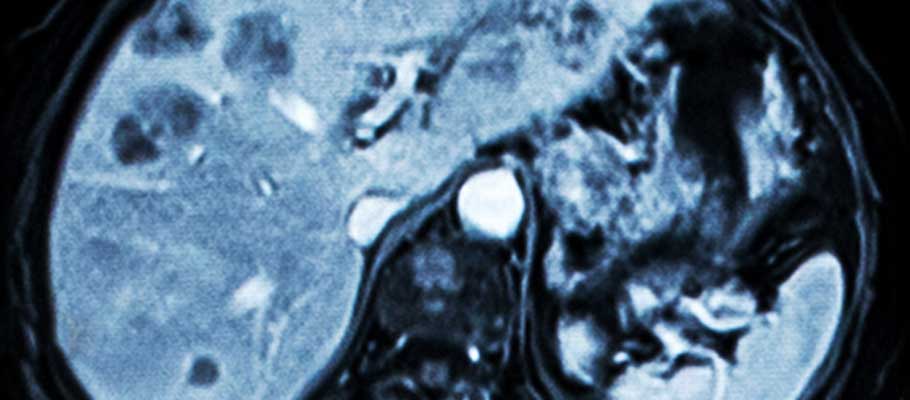

種々の疾患の自動検出

肝腫瘍・肺結節・気管支粘液栓など